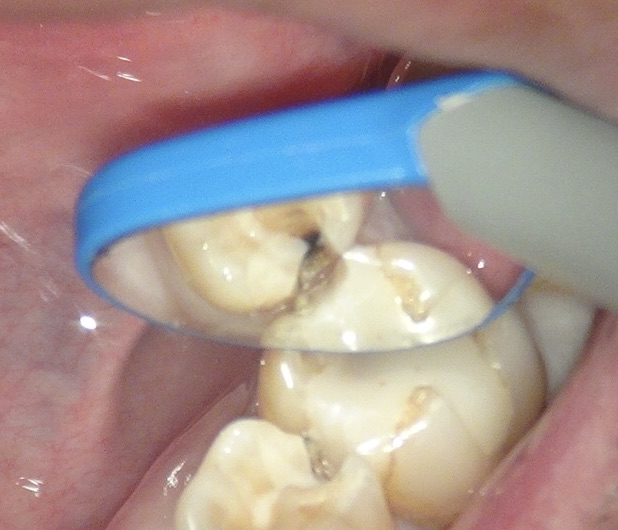

お口の中を見ると。

レントゲンの赤丸の部分がむし歯。

むし歯を取り除いていくと こんな感じになっていました。